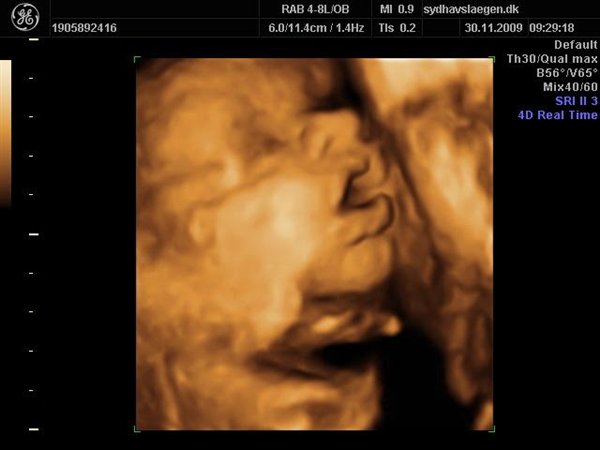

Vi skal give 1400 kr for 45 minutters total gennem scanning, hvor hun fortæller, undersøger babyen fra top til tå, laver vægtskøn også får vi billeder og dvd med hjem.... Og ja det er da mange penge, men min forlovede har haft en masse vikar timer den her mdr, også sagde han at han syntes vi skulle bruge de penge på noget vi normalt ikke ville have gjort. Han sagde egentlig at jeg kunne gå ud og shoppe for dem, men jeg har termin om ti uger, så gider ærlig talt ikke bruge penge på nyt graviditets tøj, så hellere det her som vi egentlig havde valgt fra pga prisen, men som vi begge to rigtig gerne vil....